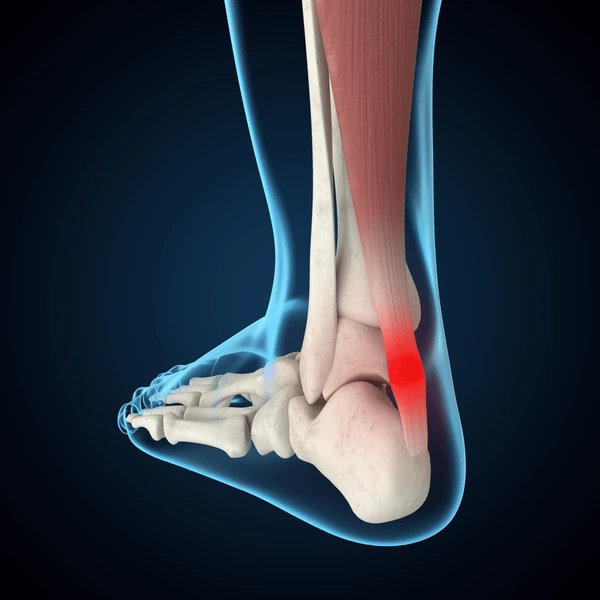

Calcaneal (Achilles) tendon

Back of ankle;

thick cord

'Achilles heel'